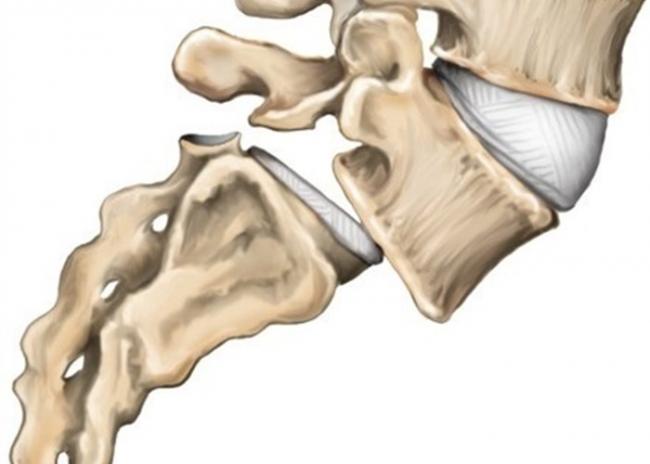

Клиновидное смещение позвонков

Клиновидное смещение позвонков впервые описано немецким хирургом, ученым Кюмелем Вернеем. Характеризуется патология как клиновидное изменение формы позвонка, дающее локальные боли. Заболевание распространено у молодых мужчин, чаще всего поражаются позвонки грудного или поясничного отдела. Причиной клиновидного смещения считается травма и само клиновидное смещение приравнивают к фазе компрессионного перелома позвонка вследствие травмы или очень сильных нагрузок.